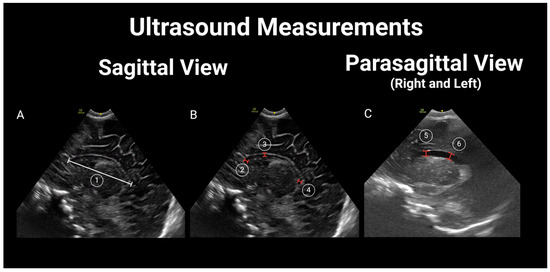

2.3. Brain US Protocol